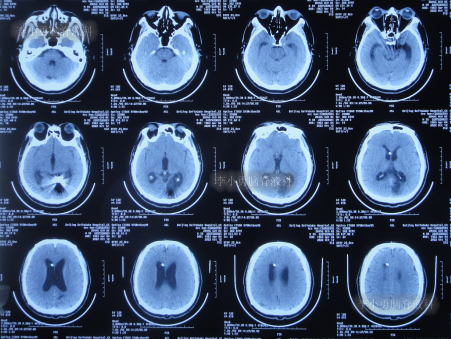

入院时查头颅CT示脑室分流术后仍脑积水(图-14)。

图-14:2022年7月22日头颅CT

入院当天拔除了原脑室分流管+脑室外引流术(图-15)。

图-15:术后头颅CT

2022年8月3日(住院治疗12天),进行了脑室腹壁外引流术(图-20)。

图-20:2022年8月3日头颅CT

2022年9月13日(住院治疗53天),常规查头颅CT示脑室引流术状态(图-22)。

图-22:2022年9月13日头颅CT

2022年10月11日(住院治疗80天),进行了脑室腹腔分流术。脑室腹腔分流术次日查头颅CT和身体均无异常(图-23)。

图-23:2022年10月12日头颅CT

2022年12月9日(李小勇脑脊液科治疗4月余)出院,出院时:身体一切正常(图-24),头颅CT未见异常(图-25)。

图-25:出院时头颅CT